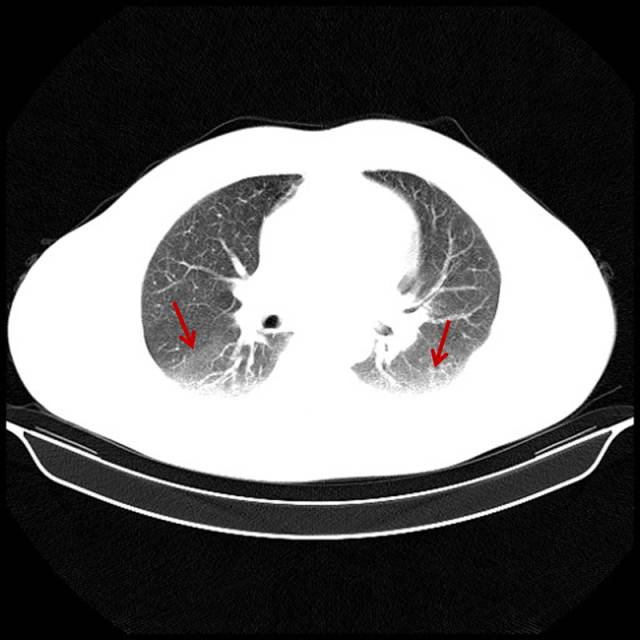

吸烟导致双肺坠积效应

男,47岁,吸烟者,每天2盒。

图片

图4

轻度肺坠积效应,这部分肺无法执行换气功能,属于亚临床患者,重度才有自觉气短症状(详细请点击→吸烟者的肺,看完果断戒烟吧!